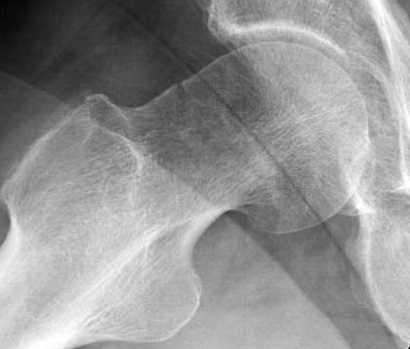

И вне контекста, еще...по классификации Devas cтрессовые переломы шейки разделяются на тензионные и компрессионные. У молодых обычно происходит по типу компрессионных переломов, они более стабильные, а у пожилых по типу тензионных (дистракционных) переломов.

Молодым дисциплинированным больным можно рекомендовать щадящее консервативное лечение на костылях. Критерием являются несмещенные переломы с обязательным частыми рентгенгенологическими наблюдениями. (См. приложенный алгоритм)

При боли в суставе, отдающее в коленный сустав, особенно у активных молодых, и кто занимается спортом, надо обследоваться на стрессовые переломы.

Снимок сустава с внутренней ротацией покажет абнормальную шейку, хотя золотым стандартом является Магнитно-резонансая томография.